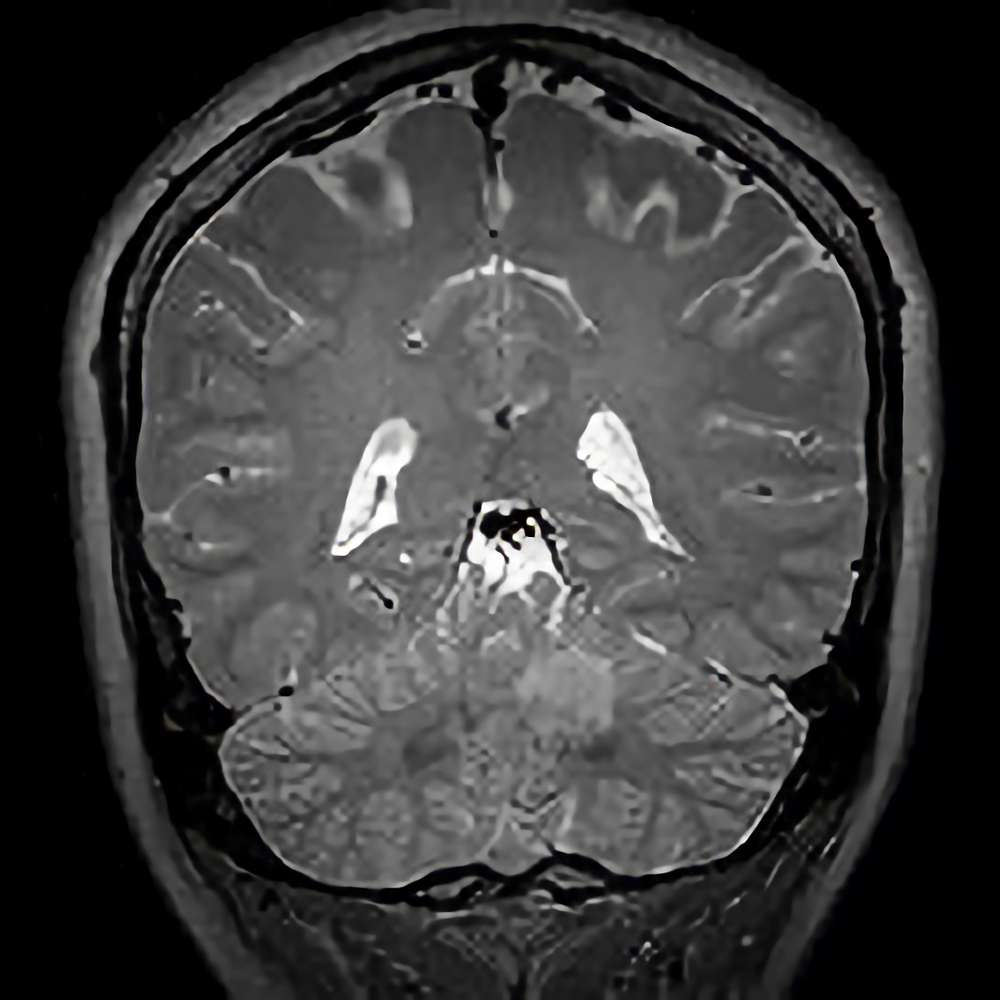

285

'22年4月

70代

膠芽腫

頭蓋内腫瘍摘出術

No.’22_42 手術前1

No.’22_42 手術前2